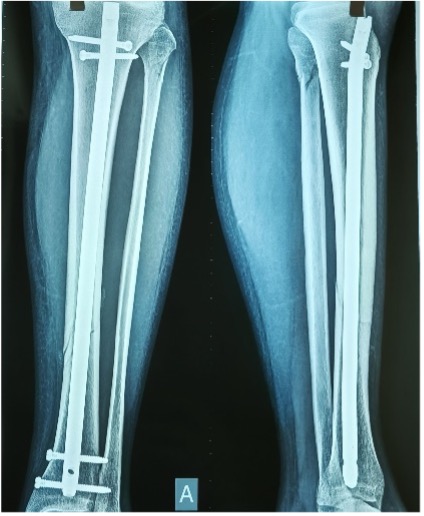

| Ακτινογραφική απεικόνιση έναν μήνα μετά τον τραυματισμό. |

Ο ασθενής μάς επισκέφθηκε έναν μήνα μετά την επέμβαση με οδηγίες για μερική φόρτιση, βάδιση με δύο βακτηρίες μασχάλης («πατερίτσες»), μειωμένο εύρος κίνησης στην ποδοκνημική άρθρωση και στην άρθρωση του γόνατος, και απώλεια μυϊκής δύναμης σε όλο το κάτω άκρο.